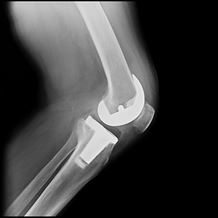

When that function is disrupted by injury or disease, knee replacement surgery may be recommended as a way to restore mobility and reduce pain. Sometimes referred to as knee arthroplasty or total knee replacement surgery, this procedure is one of the most successful in modern medicine. During surgery, any diseased or damaged parts of the knee joint are removed and replaced with artificial parts that imitate the natural movement of the knee. The most common reason for knee replacement surgery is to reduce the severe pain caused by osteoarthritis.

Total knee replacement surgery replaces the damaged parts of your knee with an artificial joint. It helps to relieve pain and restore function and mobility.